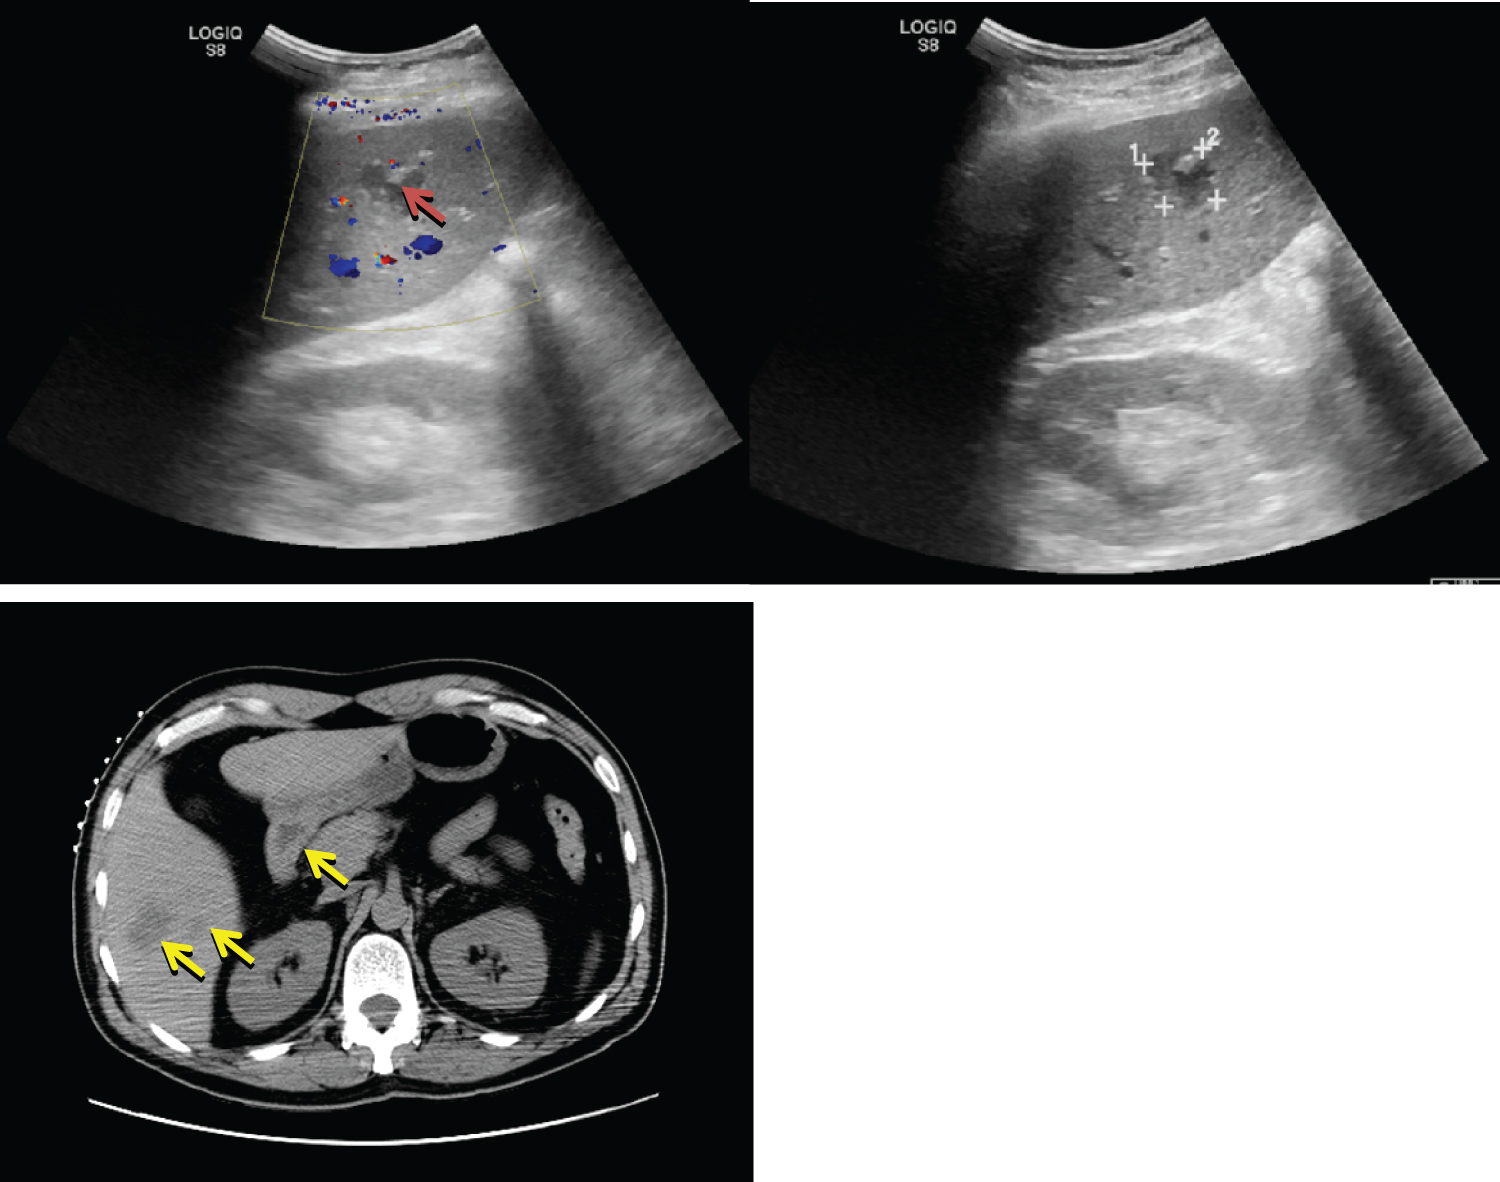

On day 3, blood cultures grew pan-susceptible K. pneumoniae. Patient was hospitalized for 9 days and workup included a CT-guided liver biopsy, also positive for pan-susceptible K. pneumoniae (culture susceptibilities in Table 1) and atypical glands with necrosis and acute inflammatory exudate. Because of multilocularity and location, a decision was made not to perform percutaneous drainage (Figure 2). Genomic testing was not available at our institution, but the clinical course was highly suggestive of KPIS and therefore it was decided to continue treatment for this entity.

Figure 2: Abdominal ultrasound & CT abdomen with contrast. Several cystic liver masses, largest measuring 3.6 cm on CT (yellow arrows), and 2.3 cm on ultrasound (red arrow). View Figure 2